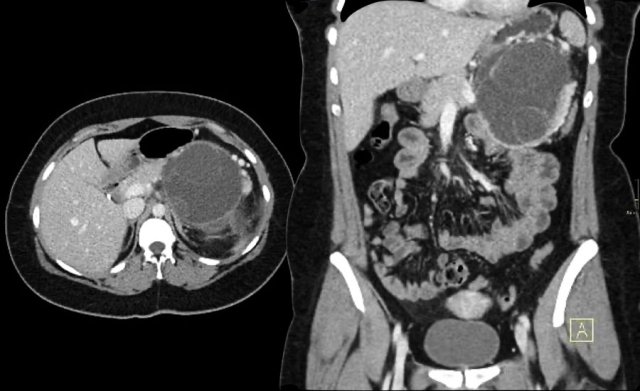

The CT demonstrates a large cyst in the upper abdomen in a patient who had an acute pancreatitis (Fig).

Notice that there is also some ascites and pleural fluid.

There is wall enhancement.

CT demonstrates two large cysts in a 45 year old woman, who had a trauma (fig).

Notice some fat stranding in the retroperitoneal space (arrow).

The imaging findings combined with the history make it very likely that these are traumatic pseudocysts.